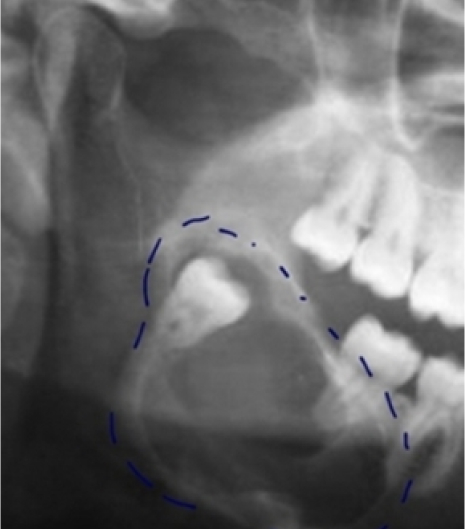

Javasoljuk, hogy amennyiben még nem tudja, mi a helyzet a bölcsességfogaival, illetve a legkisebb panaszt is érzi, forduljon szakemberhez és konzultáció mellett legalább egy röntgenfelvétel készüljön a bölcsességfogak körüli terület megvizsgálására. Bonyolult anatómiai helyzet esetén rendelőnkben elvégezhető a terület nagy felbontású 3D feltérképezése CT vizsgálattal.

A szűrés segítségével kideríthető, hogy Önnek van-e bölcsességfoga, és ha igen, akkor szükséges-e az eltávolítása. Amennyiben az eltávolítás javasolt, akkor a megfelelő röntgen vagy 3D CT felvétel abban segít, hogy az eltávolításra a bölcsességfog fejlődése során a legmegfelelőbb időpontot megtaláljuk. Egy még ki nem fejlett gyökerű fog eltávolítása egyszerűbb, gyorsabb és kényelmesebb gyógyulást eredményezhet.

Modern, alacsony sugárzású röntgenfelvételt készítünk, amellyel pontosan láthatjuk a fogak pozícióját és azt, hogy van-e elegendő hely az állkapocsban a bölcsességfog számára. Amennyiben a röntgen kérdéses vagy kockázatos helyzetet mutat, a rendelőnkben elérhető 3D CT felvétel, hogy minden oldalról megvizsgálhassuk a fogait.